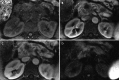

Significant advances in imaging technology have changed the management of pancreatic cancer. In computed tomography (CT), this has included development of multidetector row, rapid, thin-section imaging that has also facilitated the advent of advanced reconstructions, which in turn has offered new perspectives from which to evaluate this disease. In magnetic resonance imaging, advances including higher field strengths, thin-section volumetric acquisitions, diffusion weighted imaging, and liver specific contrast agents have also resulted in new tools for diagnosis and staging. Endoscopic ultrasound has resulted in the ability to provide high-resolution imaging rivaling intraoperative ultrasound, along with the ability to biopsy via real time imaging suspected pancreatic lesions. Positron emission tomography with CT, while still evolving in its role, provides whole body staging as well as the unique imaging characteristic of metabolic activity to aid disease management. This article will review these modalities in the diagnosis and staging of pancreatic cancer.